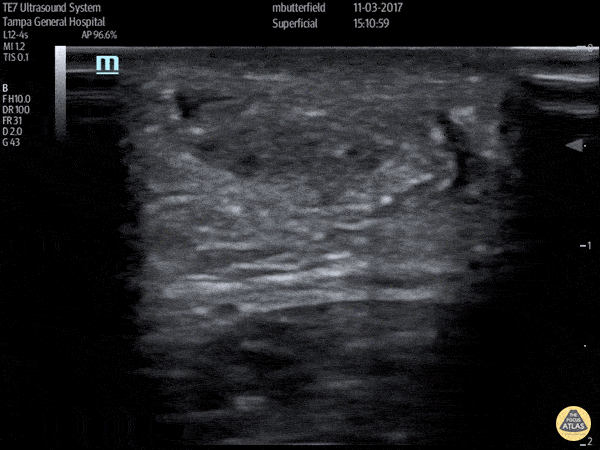

Musculoskeletal - Achilles Tendon Rupture (Short Axis)

Full thickness achilles tendon rupture of the right leg after a skateboard accident. (Short Axis) Dr. Mike Butterfield